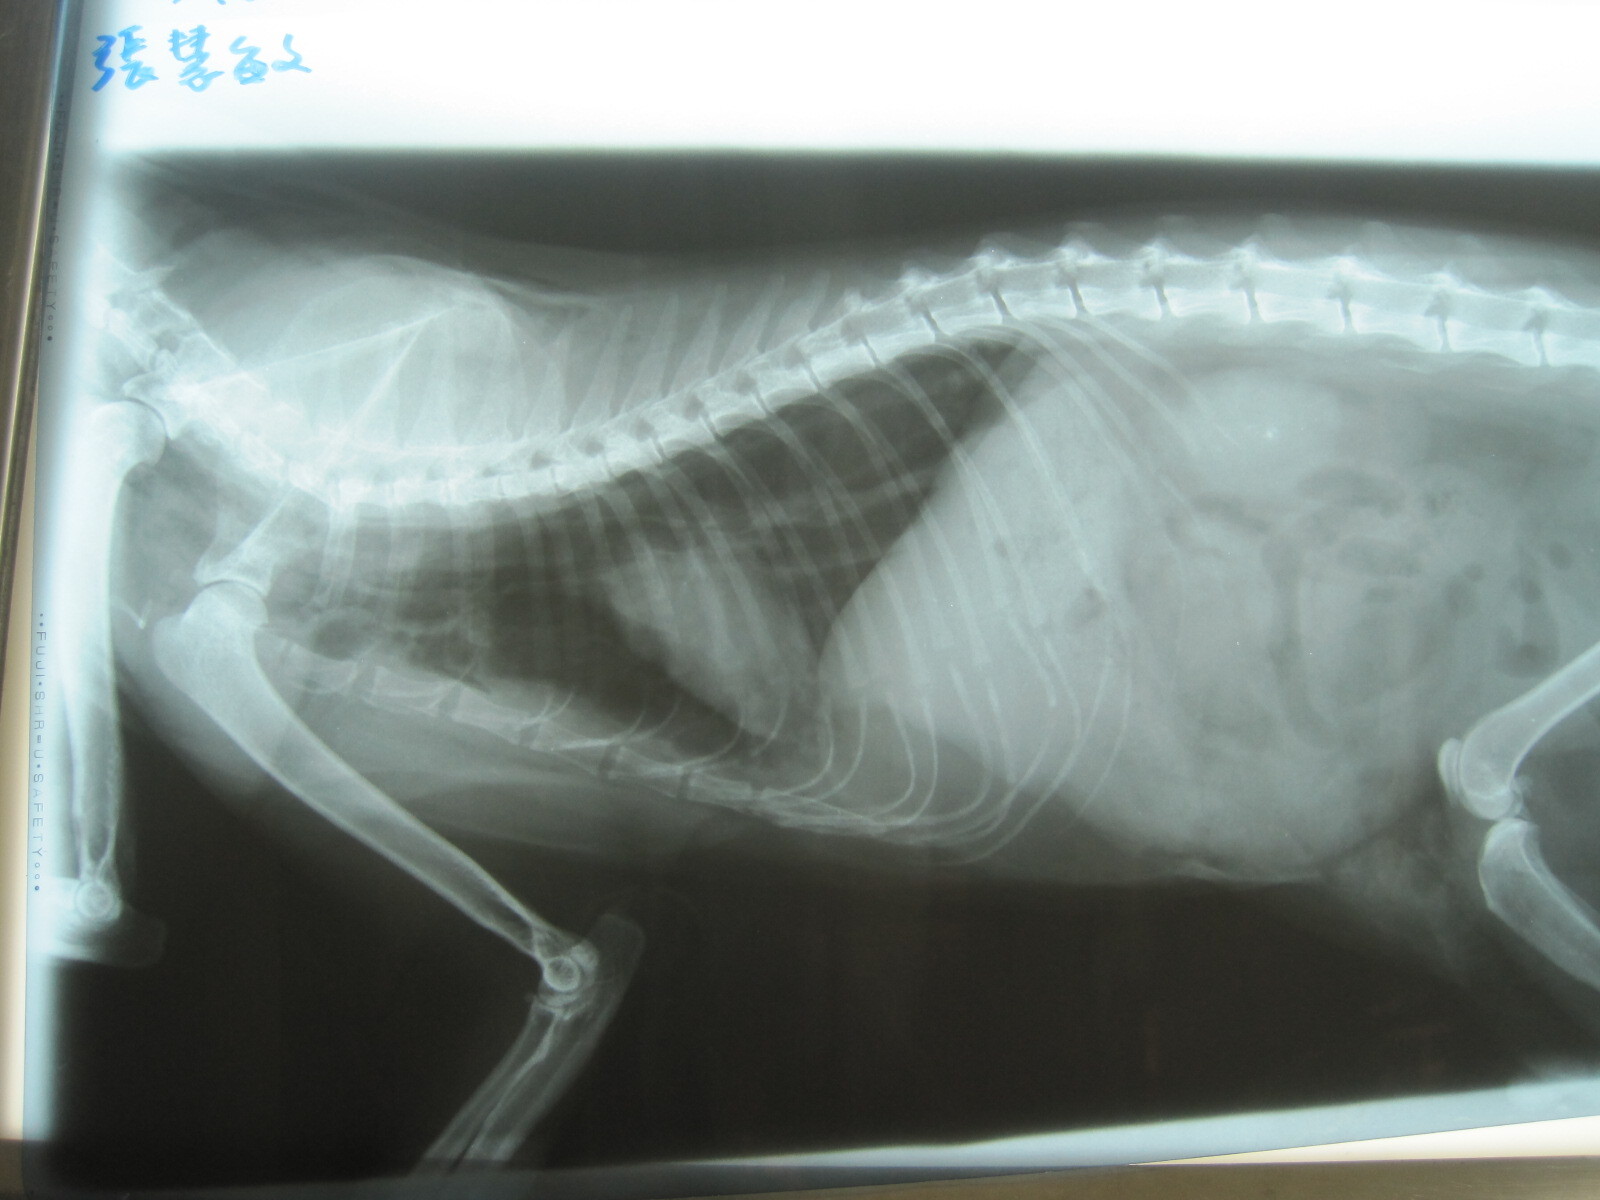

主題: 慘遭大狗咬成重傷的ㄎ一ㄎㄡㄎㄡ 申請者姓名: 張慧敏 花色: 申請日期: 2013-01-22 15:51:09 申請者部落格: 申請者臉書網址: 所在縣市/合作醫院: 台北市/詠欣動物醫院 治療費用: 5600元 需求人數: 12人 已結案 (2013-08-06 13:55:02) 報名人員: Choco Yen(已付款)、廖欣倫(已付款)、鄭古萬、Hope Liao(已付款)、Yivi Lu(已付款)、Linda(已付款)、宋小嘉(已付款)、淇勻、philip(已付款)、philip(已付款)、阿蓋 (已付款)、顏佳玲(已付款)、戴珊珊(已付款)、蔡餅乾、Shirley Tsai(已付款)、 候補人員: 動物病情說明: ㄎ一ㄎㄡㄎㄡ被大狗咬了幾口之後,已是奄奄一息,軟弱無力.鼠蹊部裂了個大洞.於是飛也似的緊急將他送醫.發現脖子附近咬了一口,氣管破了洞,有氣胸,皮下摸起來都有氣泡的感覺,腹腔也破了,一大團腸子跑到了皮下.ㄎ一ㄎㄡㄎㄡ很不舒服,血壓很低,打了好幾次才順利上點滴,緊急讓他吸氧氣和將鼠蹊部撕裂傷清乾淨和縫合.之後,住了3天的氧氣房,仍不敵死神的招喚,回天家的懷抱了.